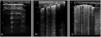

Neonatal respiratory distress syndromeRespiratory distress syndrome results from a primary (preterm neonates) or secondary (term neonates) deficiency of surfactant, and manifests with pulmonary oedema and decreased lung volume (collapse or atelectasis). It sonographic appearance is characterised by the loss of aeration with a homogeneous AI pattern and an irregular or thickened pleural line, resulting in a uniformly hyperechoic lung field (white lung),13 with condensations that may range from small subpleural collapses to large consolidations with air bronchogram (atelectasis), possibly associated with subclinical pleural effusion (Fig. 4, Video S10). Depending on the severity and course of disease, there may be different degrees of involvement in each field or hemithorax.1–3,19

Respiratory distress syndrome. A, B and C: preterm neonate born at 30+2 wk. Urgent caesarean section without prenatal steroids. Lung ultrasound at admission: (A) Anterior plane: homogeneous alveolar-interstitial pattern without areas of aeration (no A-lines) and irregular pleural line, white lung. (B) Lateral plane, similar findings. (C) Posterior plane: alveolar-interstitial pattern with pleural thickening and subpleural consolidations in lung base. (D) Transverse plane: alveolar-interstitial pattern with subpleural consolidations (arrow). (E) Posterior longitudinal plane with alveolar-interstitial pattern with pleural thickening, subpleural consolidations and consolidation with air bronchogram (atelectasis) in 2 intercostal spaces (arrow).